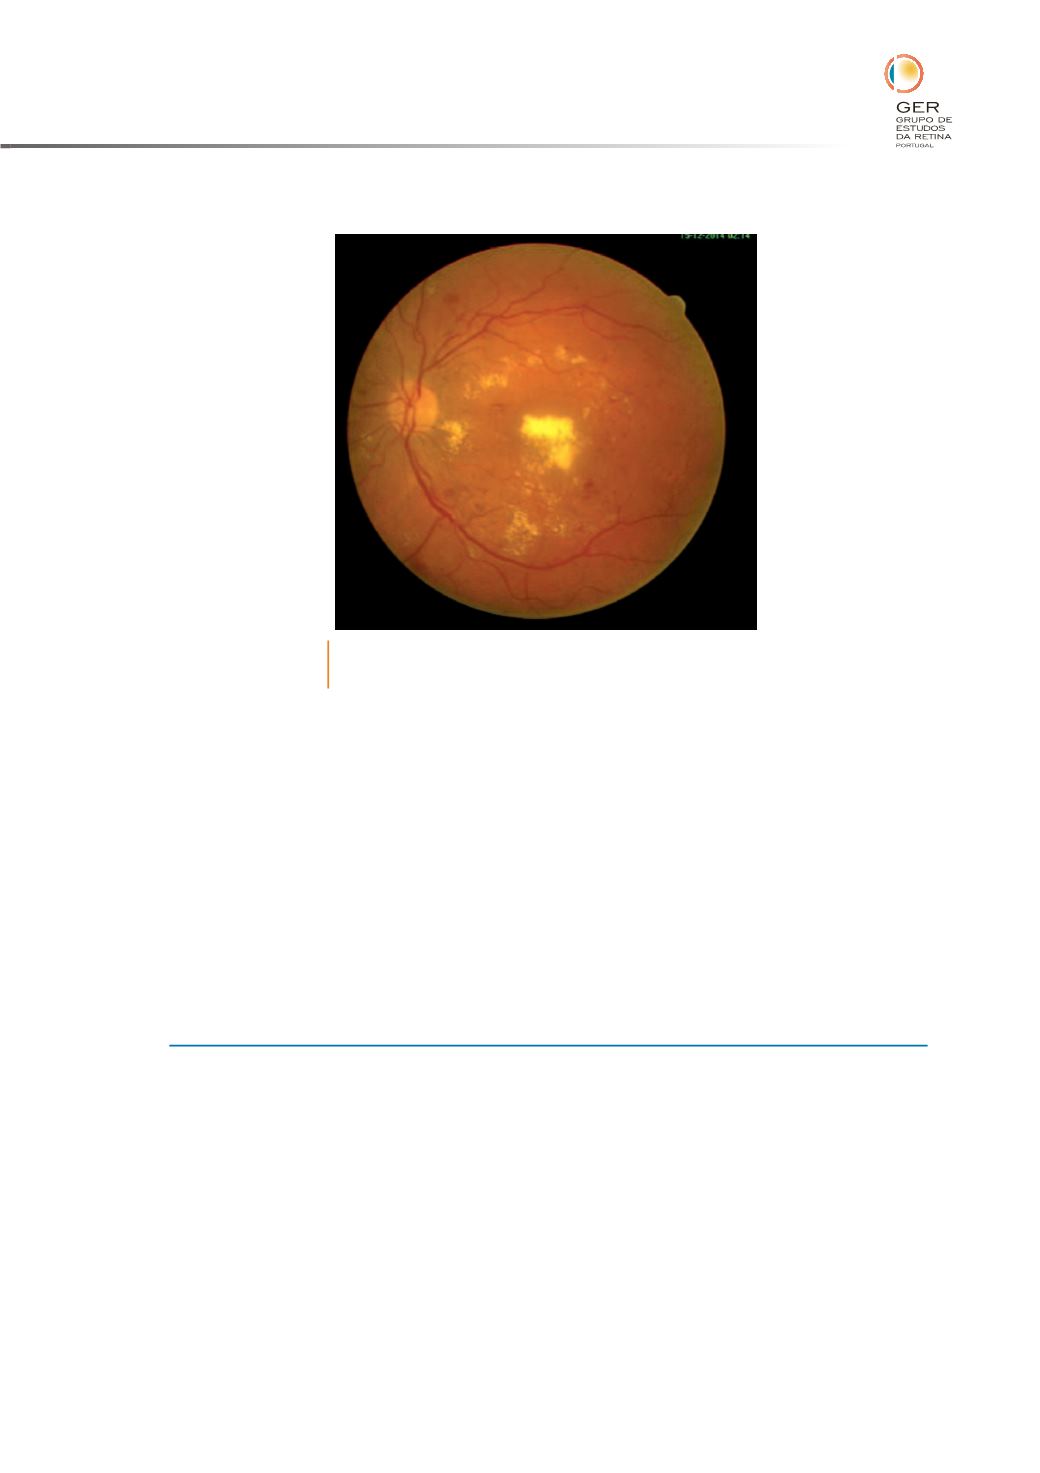

Fig. 7

O EMD grave é de%nido como a presença de exsudados duros

ou espessamento retiniano envolvendo o centro da mácula.